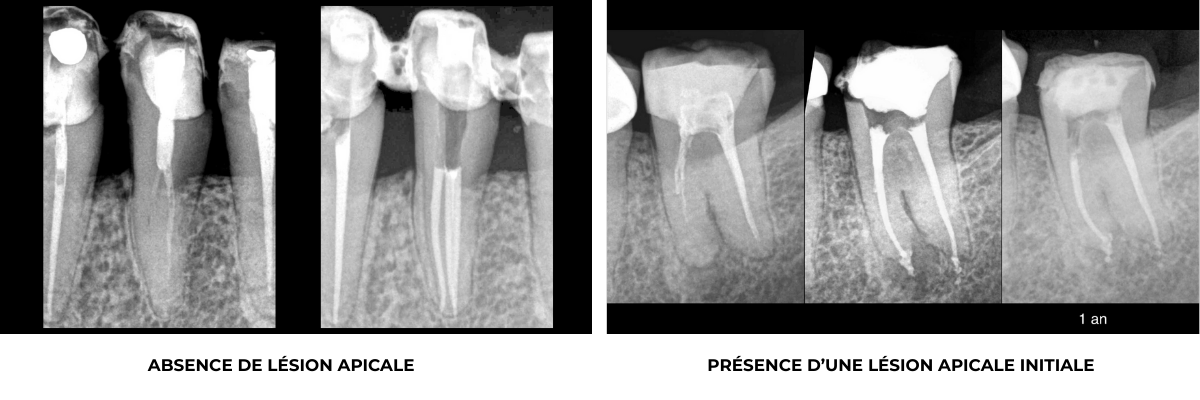

Cette nécrose pulpaire peut, si l’endodonte est infecté, avoir causé une réaction inflammatoire osseuse, c’est la lésion apicale :

En l’absence de lésion apicale, le traitement canalaire a pour objectif de maintenir la bonne santé osseuse péri apicale.

En présence d’une lésion apicale, le traitement canalaire a pour objectif de permettre la cicatrisation osseuse péri apicale.

Cas clinique

Traitement canalaire : 80-95% de taux de succès